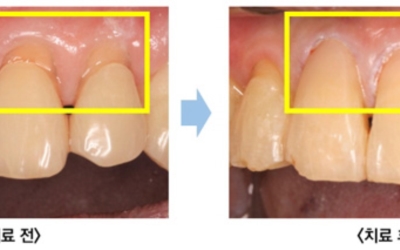

치주질환의 가장 저명한 원인은 치태와 치석입니다. 구강 내 음식물과 세균으로 인해서 치태가 형성되고, 제때 제거되지 못한 치태는 치석을 형성하고 결국 치주질환을 유발해요. 세균들이 잇몸에 염증반응을 유발하는 물질을 분비하고 이로 인해 잇몸이 붓고 잇몸에서 피가나는 증상이 생기는 것으로 보입니다.

잇몸에 발생되는 염증을 ‘치은염’이라고 부르고, 이 경우에 잇몸의 염증치료가 제때 되지 않아 염증이 악화되면 치주염으로 변하게 돼요. 증상이 악화되면 ‘치아상실’까지 초래할 수 있기 때문에 평소 잇몸관리는 필수입니다.